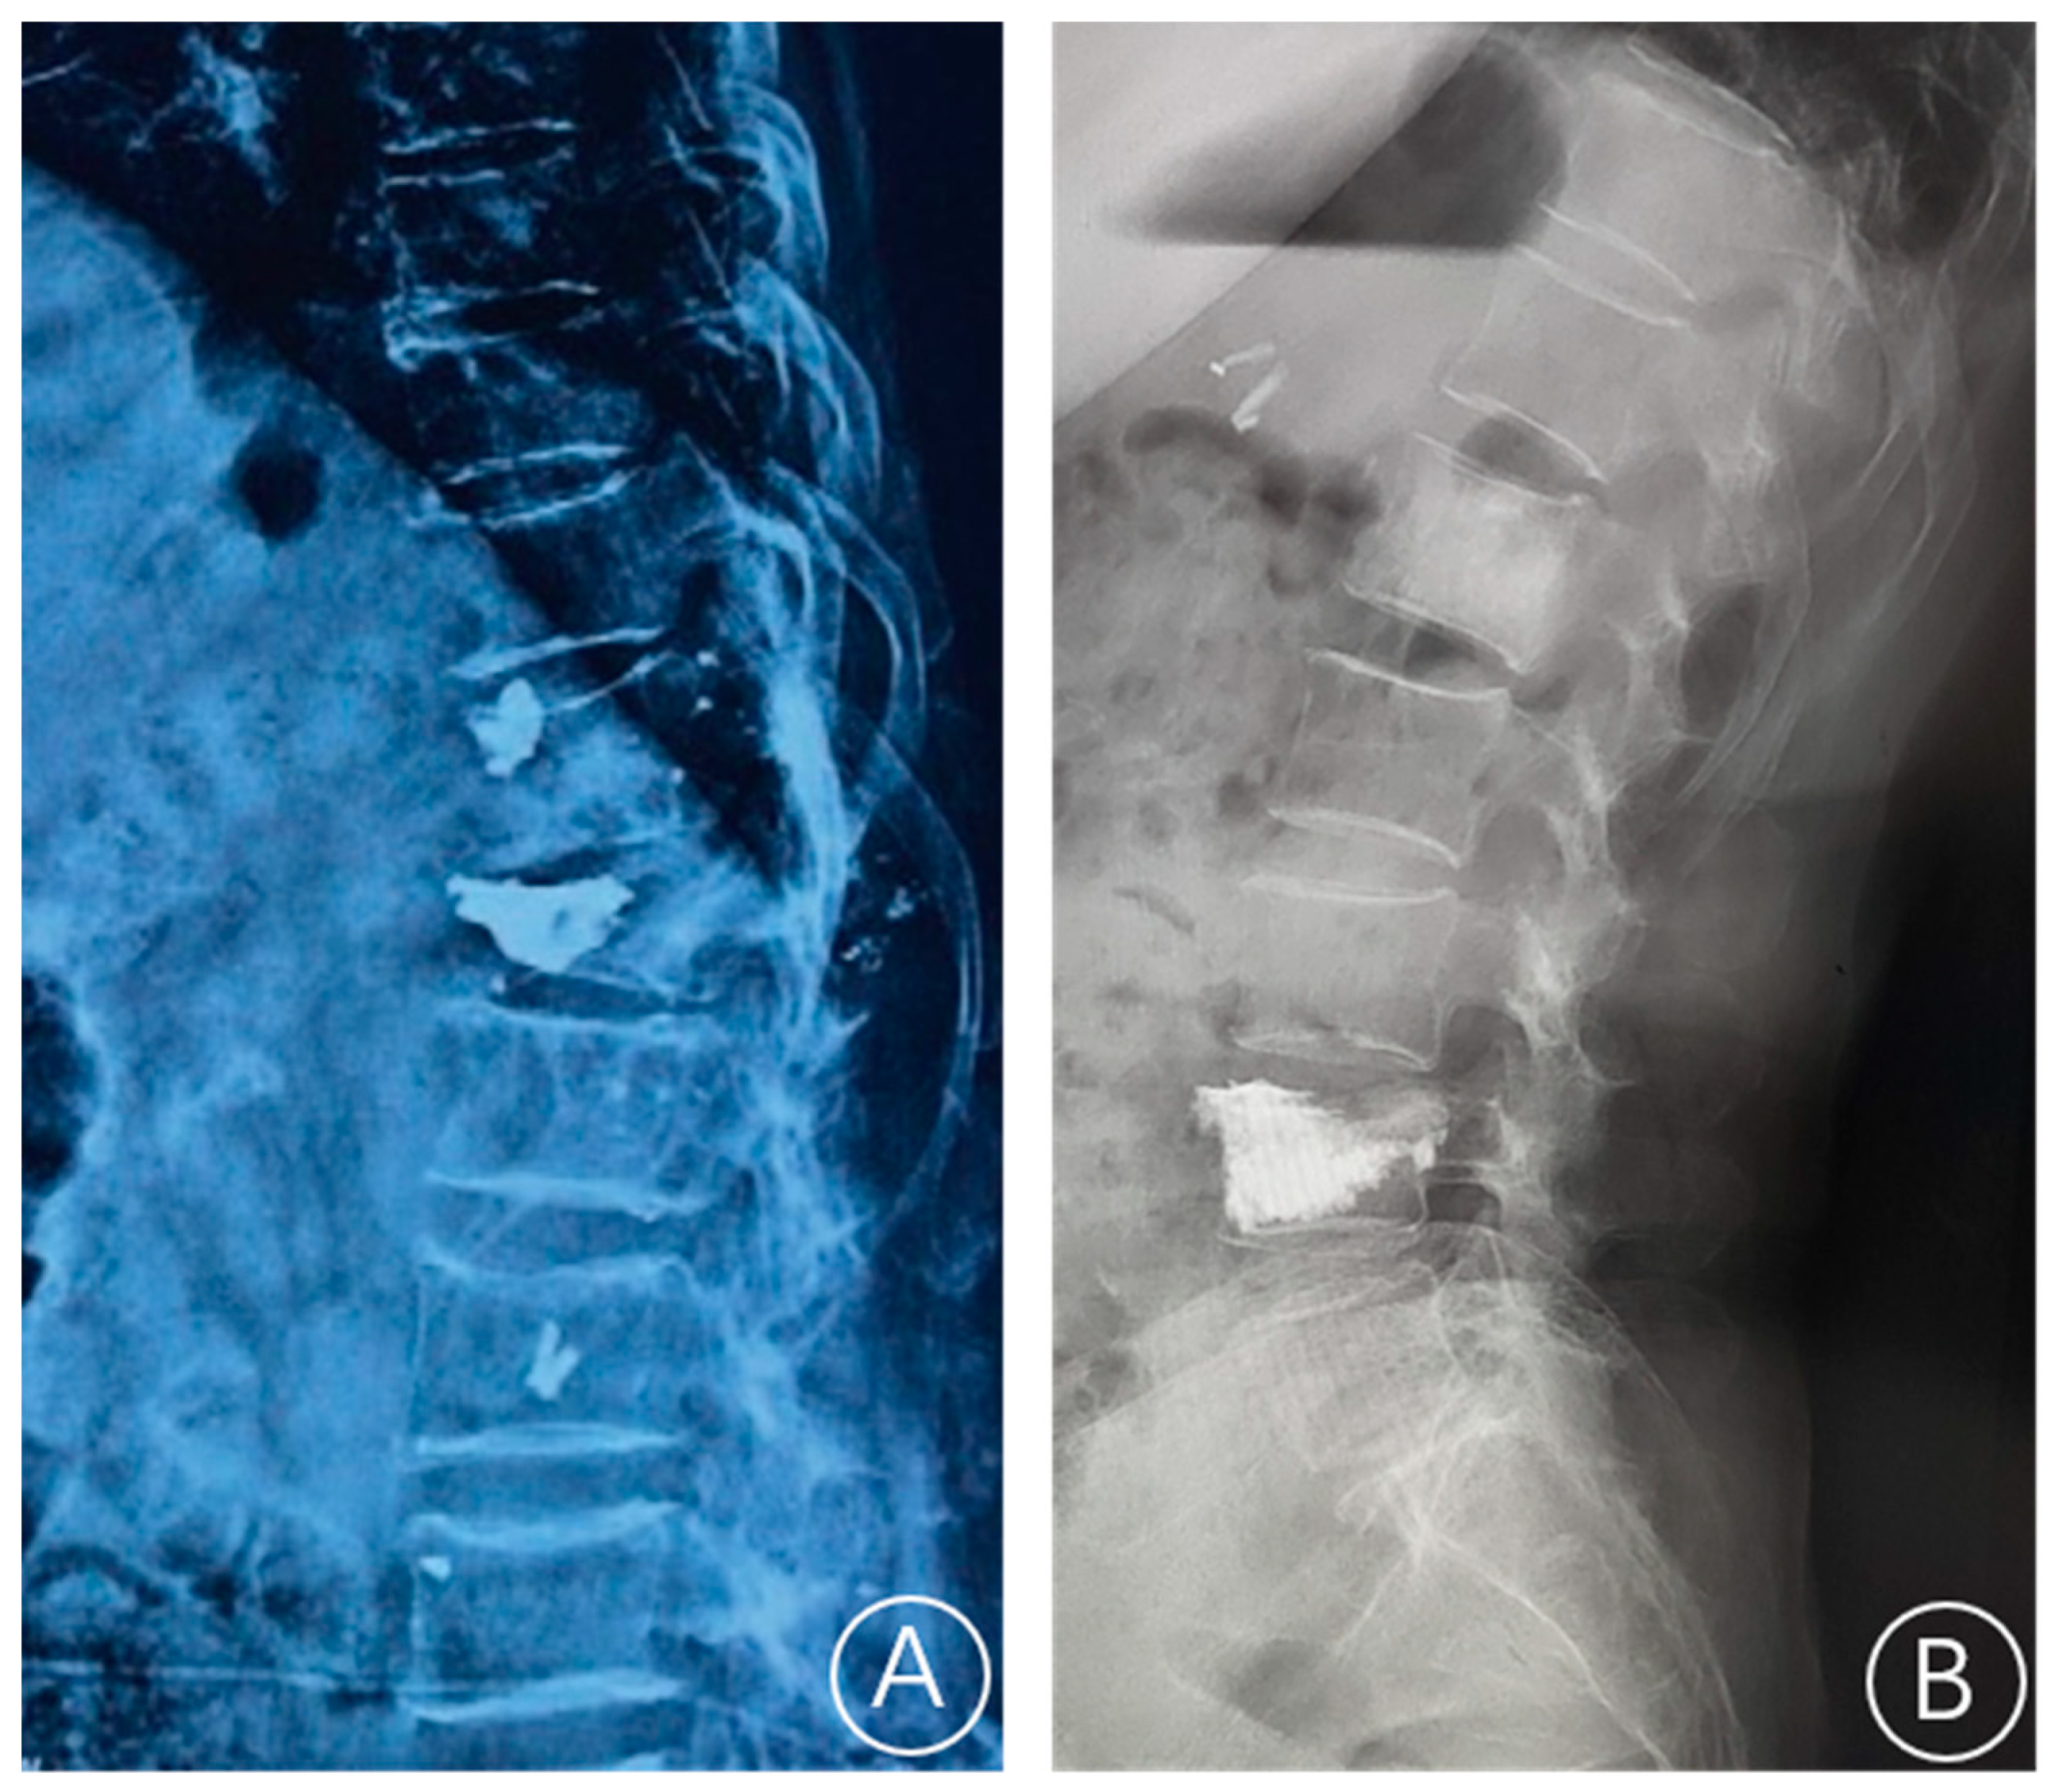

The X-ray film showed a rupture of the anterior cortex of the vertebral body and anterior displacement of bone cement (Figure 1). CT showed a rupture of the anterior cortex of the vertebral body, the anterior edge of the bone cement was more than 2 mm from the anterior edge of the vertebral body, and the bone cement moved forward. MRI examination showed vertebral collapse, and sagittal T1-weighted images and T2-weighted images of the fracture cavity showed abnormally low and high signal intensity, respectively [12]. A typical case is shown in Figure 2.

Figure 1.

A plain radiograph showed whether the bone cement is displaced. (A) Bone cement displacement. (B) Non-bone cement displacement.